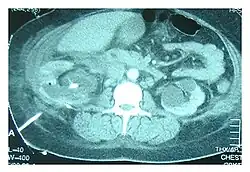

Abdominal ultrasonography and CT scan can help diagnose the underlying condition of the genitourinary tract. If other methods prove inconclusive, an accurate diagnosis can be made by a technetium-99m kidney scan, which shows albumin labeled with 99Tc that translocates into the pleural space from the genitourinary tract.[4]